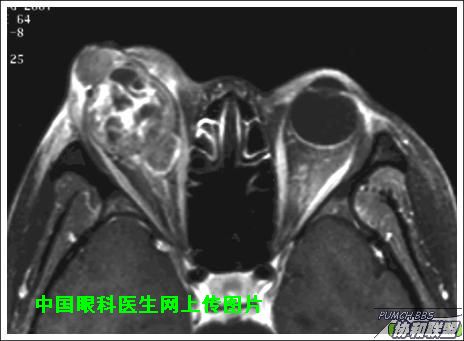

出院后半年发现右眼出现肿物,增长较快,随来京再次就诊(图1),转来我科。门诊检查发现:右眼无光感,结膜下肿物,突出睑裂。眼球突出,上移位。眶外侧可触及硬性肿物。超声(图2),CT(图3),MRI(图4,5,6)显示如图.